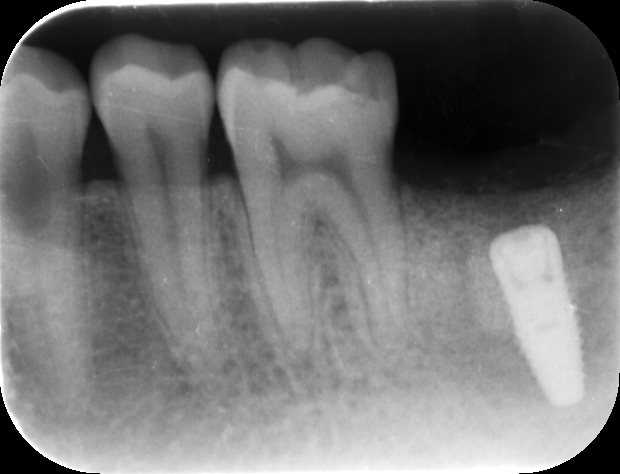

インプラントの寿命

写真は、インプラントの周りが歯周病で骨が吸収している状態になります。インプラントの周りが黒くなっているのがわかりますでしょうか?歯周病になると周りの骨が溶けてしまうので、インプラントもグラグラとゆれる様になり、最終的には脱落してしまいます。